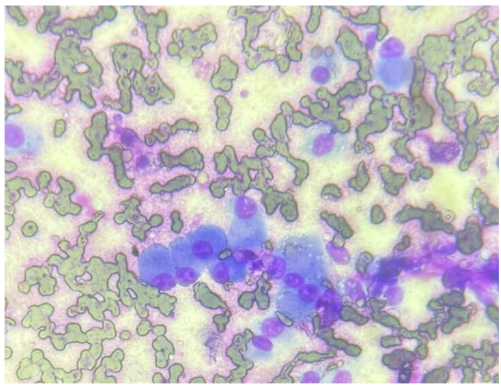

Diagnostics may include immunohistochemistry, special staining for ALP activity, flow cytometry and PARR. The latter two diagnostics are especially useful to evaluate lymphoid neoplasia, whether lymphoma or leukemia. In contrast to some mesenchymal cells, osteoblasts (the cell of origin for osteosarcoma) tend to exfoliate well (Fig. 1).

Classic cytologic descriptions of osteosarcomas may include moderate to high numbers of plump mesenchymal cells in a densely granular eosinophilic background with varying amounts of an extracellular pink wavy or amorphous matrix material in association with the neoplastic cells (Raskin and Meyer, 2016; Etzioni, 2022). Individual neoplastic cells are oval to rounded with moderately basophilic cytoplasm, with/without a perinuclear clearing/Golgi zone and flecks of atypical mitotic figures may be observed in some neoplastic and multinucleate cells. Nuclei are extremely eccentric, often appearing as if in the center of the cell, and are usually one to two prominent nucleoli.

Osteoclasts

The presence of osteoclasts must also be considered. When osteoclasts (Fig. 5) are seen, indicates bony lysis is likely occurring. However, bony lysis may occur in neoplastic and non-neoplastic lesions. With inflammation of the bone, lysis may occur. Thus, seeing this cell type does not constitute a diagnosis of neoplasia. Since osteoclasts are charged with cleaning up bone, variable numbers of them may be seen in osteosarcomas, mixed mammary tumors and osteomyelitis. They may also be a part of the process of remodeling bone during fracture healing and during normal growth in animals and humans. Additionally, giant cells may be mistaken for osteoclasts and may be a feature of feline and less commonly canine osteosarcomas cytologically and histopathologically (Pool, 1978).